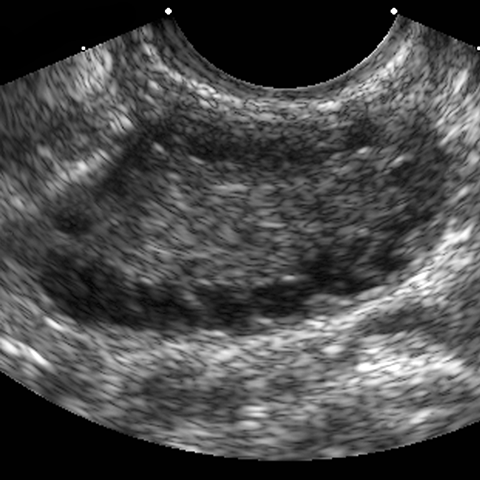

28 year old female with excessive hair growth on her face and abdomen presents with irregular vaginal bleeding. [1 of 2]